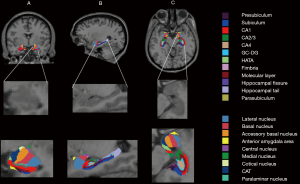

Hippocampus sub-regions segmentation

Thirteen subfields were obtained for hippocampus: cornus ammonis (CA)1, CA2/3, CA4, molecular layer, alveus, GC-DG, HATA, subiculum, presubiculum, parasubiculum, fimbria, hippocampal tail, and fissure.

According to the location and pyramidal layer thickness, subiculum, CA1, CA2, CA3 were defined: the widest region is subiculum, the thinner is CA1, and then is CA2, and CA3 is thinner than CA2. Since the contrast is not clear, the CA2 and CA3 were combined, and because of the thin shape and unreliable division removed alveus volume in this study (29). The presubiculum lies between the subiculum (laterally) and the parasubiculum (medially). CA4 sub-regions locates within the dentate gyrus and fills the inside of the GC-DG label. The GC-DG consists of a polymorphic layer, a molecular layer, and a granule cell layer. The molecular layer lies above the subiculum and underneath the hippocampal fissure. The hippocampal fissure opens medially and extends laterally until there is residual space between the molecular layer of hippocampus and dentate gyrus. The fimbria, which is a white matter structure, lies in the mid-body of the hippocampus. HATA is superior to the other subfield and locates in the median region. More detailed information about the segmentation method could be found in the literature of Iglesias et al. (29).

Amygdala sub-regions segmentation

In total 9 nuclei were segmented for the amygdala, including lateral, basal, accessory-basal, anterior-amygdaloid-area (AAA), central, medial, cortical, corticoamygdaloid-transition (CAT), and paralaminar nucleus. The lateral nucleus is the largest nucleus and the first to appear in the anterior portion of the amygdala. Following the lateral nucleus, the basal nucleus appears. The medial border of the amygdala is CAT, laterally bordering AAA, accessory-basal, basal, paralaminar, and central nucleus along with the anterior-posterior extent. The AAA lies the anterior end of the amygdala, bordering CAT anteriorly and laterally. The central nucleus is between basal nucleus laterally and CAT medially, which appears circular and dasal to accessory basal. The medial nucleus covered nearly all of the lateral-dorsal boundary of CAT. The Cortical nucleus appears as a small circular nucleus, which borders accessary-basal. The paralaminar nucleus borders the basal and lateral nucleus, which is a small, light band. More detailed information about the segmentation method could be found in the literature of Saygin et al. (28).